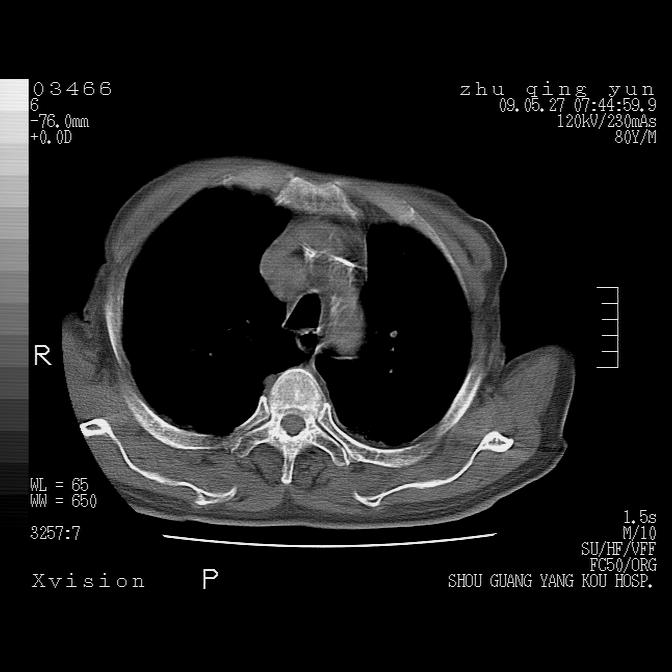

病人男性,年龄80,气喘来院,其他病史不太详细,1月前有过恶心,呕吐,在当地人民医院做过钡餐,诊断胃炎,

1)考虑左肺中央型肺癌并阻塞性肺炎,后下纵隔受侵伴纵隔淋巴结转移。2)双侧少量胸腔积液,胸膜增厚。3)心包积液。

左侧中心型肺癌并纵隔淋巴结广泛转移.心包积液

左肺下叶见多发片状及结节状病灶,左肺基底段支气管闭塞,纵隔内见多发淋巴结肿大,纵隔向左侧移位,左侧胸廓变小。应该是左肺下叶中心型肺癌,纵隔淋巴结转移,左侧肺内转移,左肺基底段肺不张,阻塞性肺炎。

1)考虑左肺中央型肺癌并左肺下叶阻塞性肺炎、不张;左胸膜腔积液、心包积液、纵隔淋巴结转移;癌肿累及左心房。2)左心室大。冠状动脉壁钙化斑。